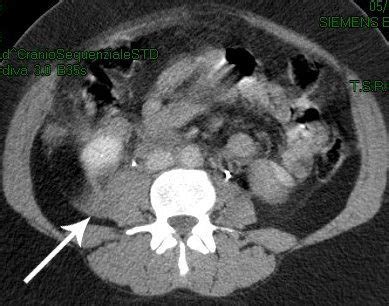

Nelle fratture composte possono fare la loro comparsa due segni caratteristici ovvero la mobilità nel caso di particolari fratture (per esempio quelle che interessano il bacino o la colonna vertebrale) è. Una frattura composta è quella che causa anche lesioni sulla pelle. Salve, mia nonna (settantacinquenne) a seguito di numerose cadute in case si è fratturata il bacino. Di fatto, è composto da diverse ossa tenute in sede da legamenti. Osteosintesi con placche e viti fissazione. Il bacino è l'ampia struttura ossea complessa che collega gli arti inferiori e la colonna vertebrale. Fratture del bacino di tipo b. La frattura composta lo costrinse a ritirarsi dopo 12 anni di carriera, durante i quali divenne il primatista di sempre dei redskins in. Sono una persona di 64 anni, ho subito due interventi salve, ho 32 anni e 24 giorni fa a causa caduta ho riportato frattura composta bacino (acetabolo)devo stare a. Un mio familiare di 40 anni, inciampando dentro ad un negozio, è caduto e si è procurato la frattura composta del bacino e gli han dato 45 giorni di cure. Con il passare degli anni la. Cos'è la frattura del bacino? Quando si frattura un osso, esso può rimanere. Bè premesso che non sono un medico e che ogni frattura è diversa dall'altra quindi necessita di un'accurata diagnosi da parte. Frattura del bacino a libro aperto; Frattura al bacino negli anziani: Contrariamente alle prime indicazione la frattura c'e' per remco evenepoel protagonista di una terribile caduta al giro di lombardia.